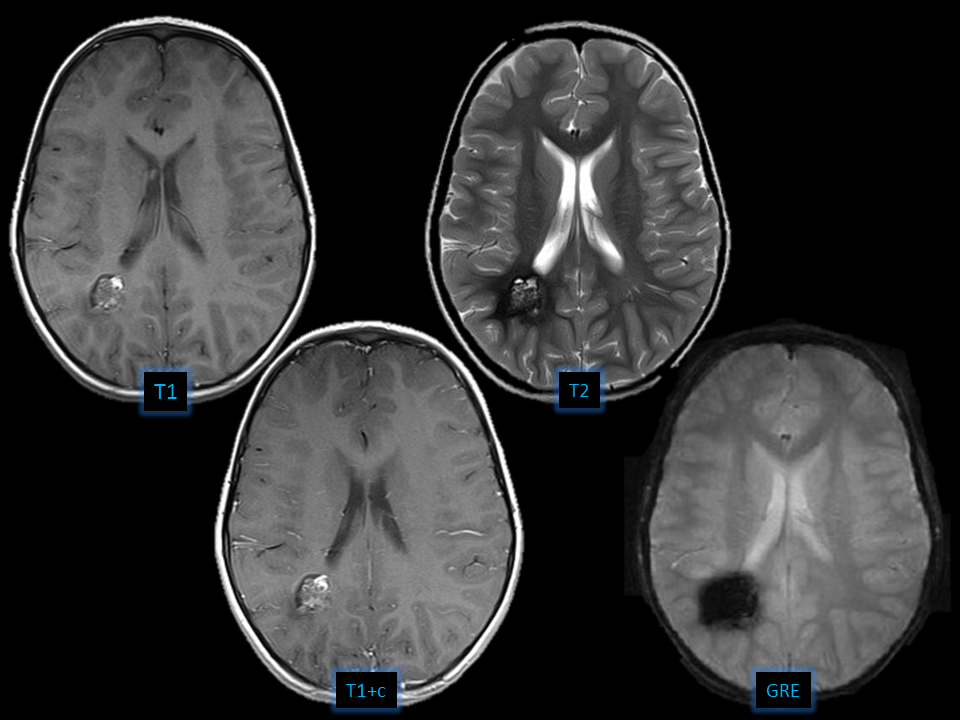

– Heterogeneous mass

– IntrinsicT1 and lowT2 margin

– Blooming artifact atGRE

– Cavernous malformation

– Diffuse axonal injury

– Arteriovenous malformation

– Hemorrhagic neoplasm

Cavernous Malformation

- Cavernous Malformation = cavernoma, cavernous angioma, cavernous hemangioma

- Benign sporadic or familial low pressure vascular lesion with bleeding propensity

- Locules of blood in different phases

- 50% have calcification

- show T2* GRE blooming artifact

- Asymptomatic-Seizures,Major hemorrhage

- Associated with developmental venous anomaly